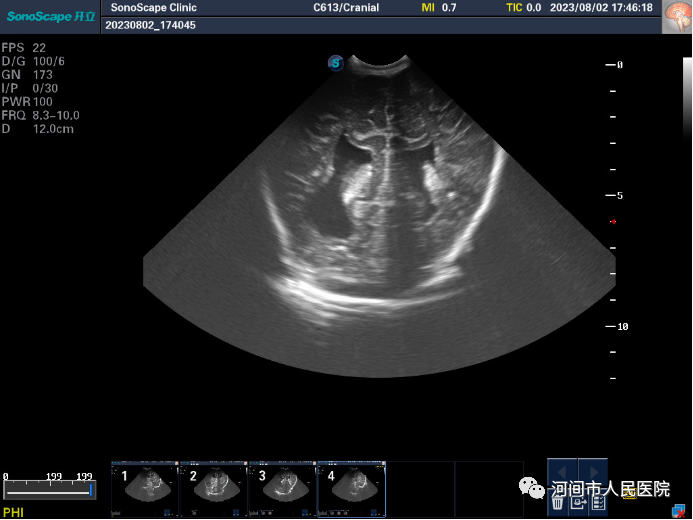

▲正常图像

▲新生儿室管膜下囊肿

▲新生儿脑室内出血

▲新生儿缺血缺氧性脑病

▲新生儿脑积水